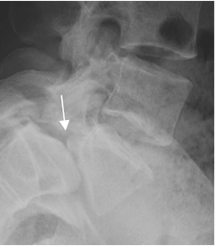

Fig 76. Inestabilidad.

A: Rx lateral neutra y B: Rx lateral en flexión. Anterolistesis GI de L5, sobre S1, que aumenta en la proyección de flexión e indica inestabilidad.